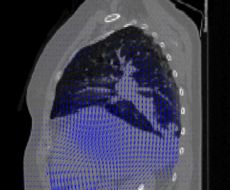

Deformable Registration

Accurate assessment of radiation dose to the thorax and abdomen during respiration requires simulation of a static beam that irradiates a moving and deforming target. The goal of this project is to use deformable registration for radiation dose calculations in these sites.

We currently use standard deformable registration tools (B-splines, RBF, optical flow), but they are not as reliable as they could be. There are many approaches to improve: especially using interactive tools for validation and using segmented regions for guidance.

2D-3D Registration

Patient positioning is performed by matching a 2D image with a 3D scan. This process can be automated with 2D-3D registration. Sub-areas of potential interest are (1) Portal imaging, (2) orthogonal rigid matching vs. 3-D cone-beam deformable matching.